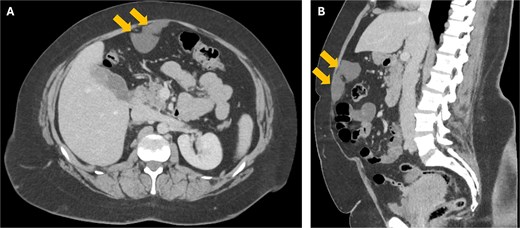

A 38-year-old woman presented to clinic with chronic supraumbilical abdominal pain. This was not associated with any gastrointestinal or constitutional symptoms, or systemic unwellness. She did not have any significant medical history. She had a Caesarean section 5 years prior. On examination, a large mass was palpated in the supraumbilical area; there was a small reducible fat-containing umbilical hernia, and there were no signs of peritonism. Blood tests including serum tumour markers were unremarkable. Computed tomography (CT) of the abdomen revealed an 8 × 3 cm hypodense lesion just deep to the anterior abdominal wall (Fig. 1). An ultrasound (USS) characterised this lesion as an 8 × 7 × 3 cm cyst with simple internal contents suggestive of a falciform ligament cyst (Fig. 2).

A USS image showing the 8 cm falciform ligament cyst with simple internal contents.